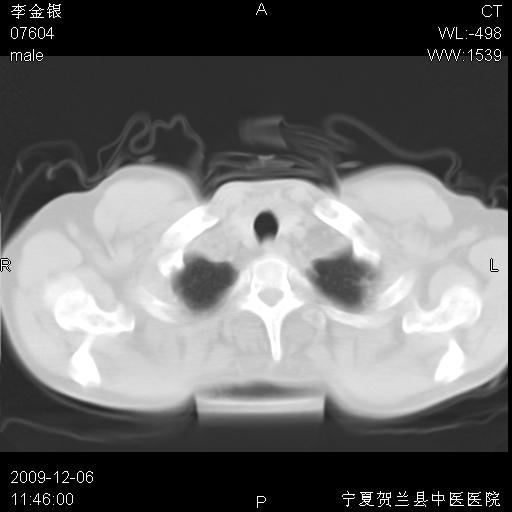

该病人 ,男,62岁,主因咳痰带血两天

考虑右肺中央型占位性病变并阻塞性肺炎.(右肺上叶支气管变窄),建议支纤镜检查.

支气管壁明显增厚 管腔狭窄,腔静脉后多个淋巴肿大,结合年龄病史考虑右肺上叶中央型肺癌并阻塞性肺炎

右肺上叶后段支气管阻塞,右上肺门占位,相应肺段阻塞性肺炎,右肺门有淋巴结肿大。诊断右肺上叶中心型肺癌,阻塞性肺肺炎、右肺门淋巴结转移。

右上叶支气管狭窄,管壁增厚,远端斑片状软组织影,病灶邻近叶间裂,叶间裂无移位。

诊断右肺中央型肺癌。

那个片影应该大部分都是病灶,病灶沿肺段支气管分支生长,后段完全显示不清、闭塞。若为不张应该伴有叶裂的移位,若为炎症应有空气支气管征。